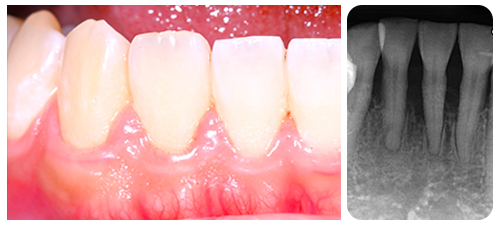

初期:歯肉炎

口の中の細菌が増えるにつれて、歯周ポケットの部分に炎症が現れます。歯肉が赤く腫れ、出血が起こります。これが歯肉炎です。

歯肉炎の治療法は、歯周ポケット内の細菌がブラッシングにより減少すれば1週間から10日でなおります。適切なブラッシング指導を受けてください。

中期:歯周炎

歯肉炎の状態が続くと、歯周ポケット内の歯周病原菌の活動により、歯と歯肉の間の結合組織を徐々に壊され、歯周ポケットが深くなります。このとき生体の防御力は、喫煙やストレスなどの危険因子によって、大きく作用されます。

歯周病の初期の段階が歯肉炎で、歯周炎とは、炎症が深部組織に侵攻し歯周靭帯(歯根膜)が壊され、続いて歯槽骨(顎の骨)が吸収していく骨の病気でもあります。